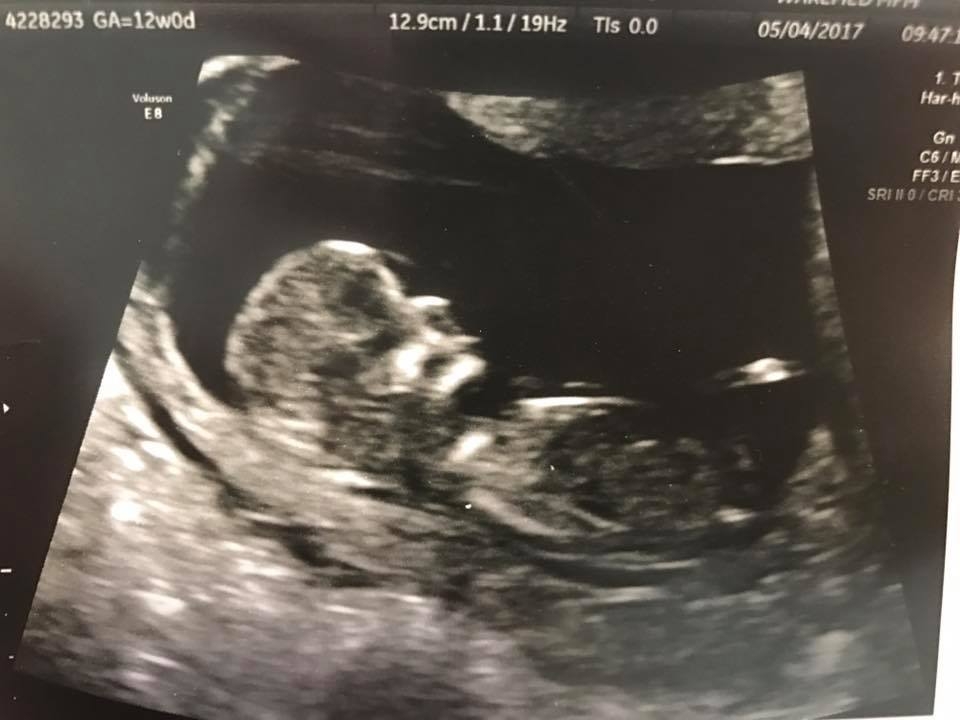

1. How far along are you? What is your EDD? 12 + 4